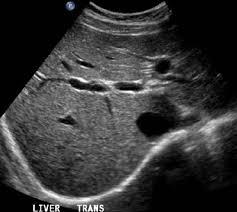

Η διάγνωση της αλκοολικής νόσου του ήπατος πολλές φορές δεν είναι εύκολη, κυρίως επειδή οι ασθενείς υποτιμούν την ποσότητα αλκοόλ που πίνουν και πολλές φορές κρύβουν την αλήθεια. Επίσης οι εργαστηριακές εξετάσεις και η κλινική εικόνα δεν δείχνει πάντα ξεκάθαρα ευρήματα γιατί τα ίδια μπορεί να φανούν και σε άλλες παθήσεις. Σε γενικές γραμμές οι τρανσαμινάσες (ιδίως η AST) καθώς και η ggt είναι αυξημένες και στον υπέρηχο μπορεί να φανεί πως το ήπαρ είναι διογκωμένο, ότι έχει λίπος, ή στα πολύ προχωρημένα πως έχει κίρρωση ή καρκίνο.